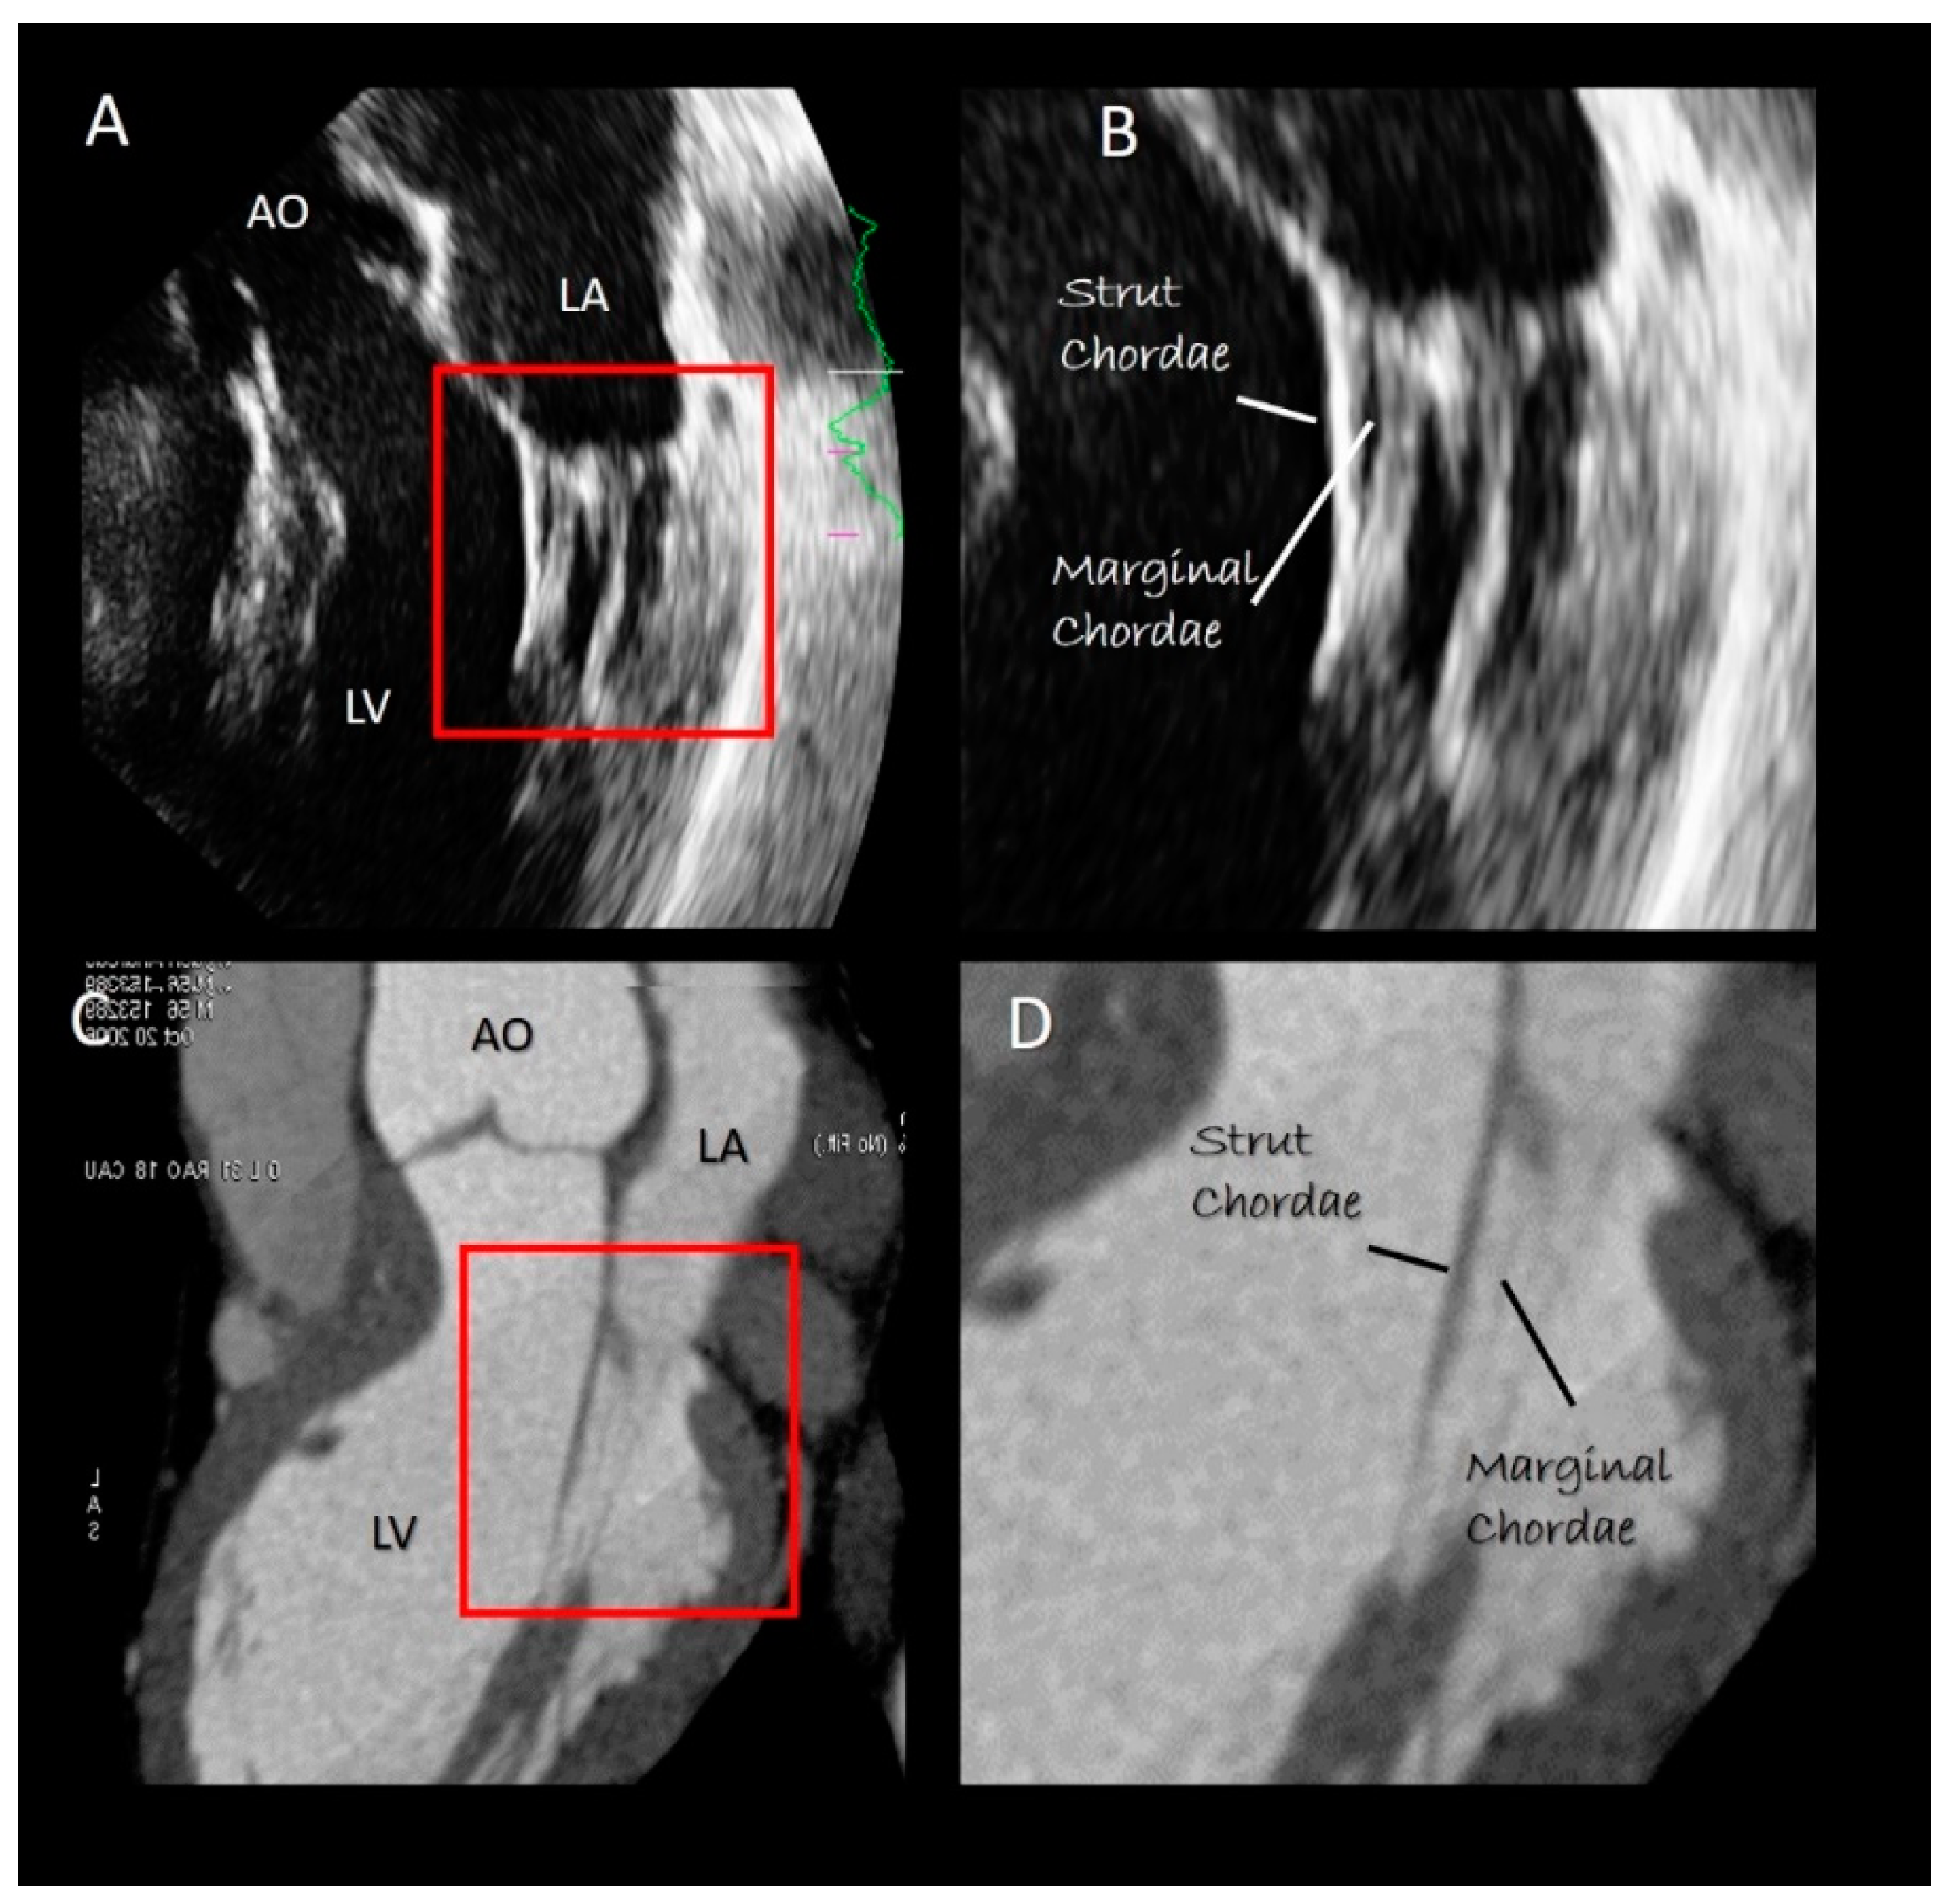

4. Chordal Apparatus

Imaging Techniques